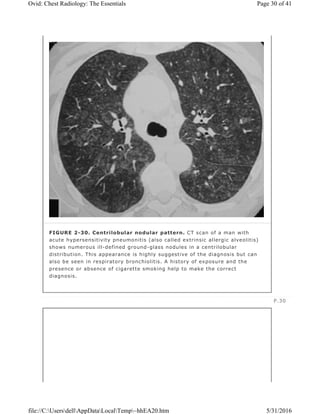

FIGURE 2-30. Centrilobular nodular pattern. CT scan of a man with

acute hypersensitivity pneumonitis (also called extrinsic allergic alveolitis)

shows numerous ill-defined ground-glass nodules in a centrilobular

distribution. This appearance is highly suggestive of the diagnosis but can

also be seen in respiratory bronchiolitis. A history of exposure and the

presence or absence of cigarette smoking help to make the correct

diagnosis.

of GGO in a centrilobular distribution are characteristic of the acute or subacute

stage of extrinsic allergic alveolitis (Fig. 2-30) or respiratory bronchiolitis. The

nodules are poorly defined and usually measure less than 3 mm in diameter. A